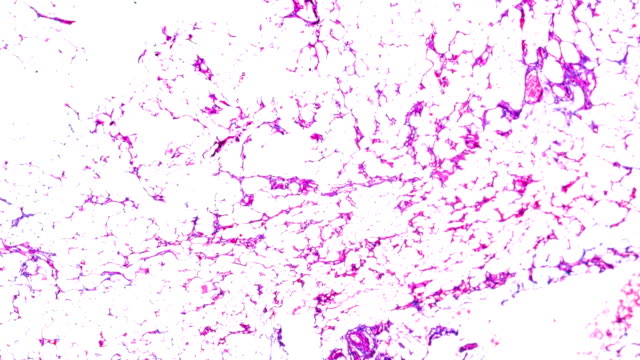

말랑한 혹이 피부 밑에서 만져진다면, 이것은 지방종일 가능성이 높습니다. 지방종은 피부 아래 지방 세포들이 한데 모여 혹 형태로 나타나는 피부 질환입니다.

이 혹들은 주로 말랑하고 손으로 만져집니다. 그럼에도 불구하고, 왜 이러한 혹들이 발생하는지에 대한 정확한 원인은 아직 알려지지 않았습니다.

지방종은 피부 아래에 있는 지방 세포들의 일부가 모여 혹을 형성하는 것으로 보입니다. 그러나 왜 이러한 지방 세포들이 한데 모여 혹을 형성하는지에 대한 과학적인 설명은 아직 없습니다. 몸무게나 지방 중량과 지방종 간의 직접적인 관련성도 발견되지 않았습니다.